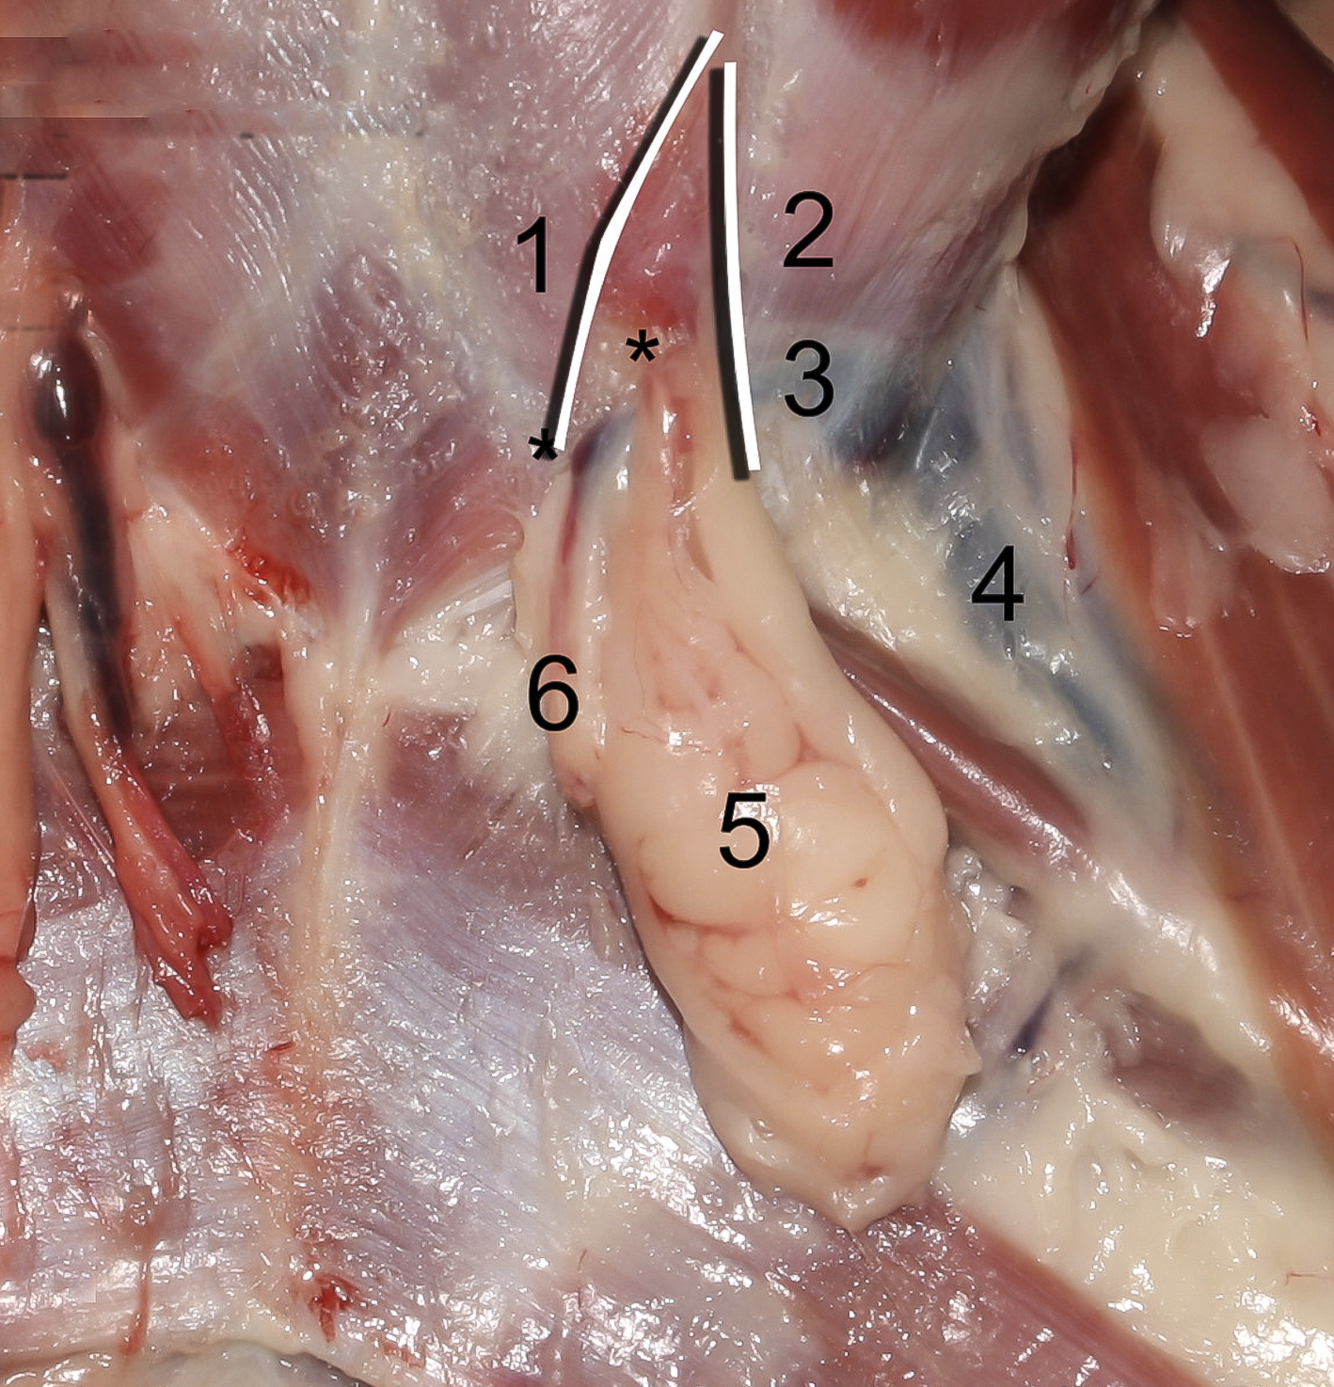

Q

1

A

Crus mediale

6

Q

2

A

Crus laterale

7

Q

3

A

A./v. pudenda externa

8

Q

4

A

A./v. femoralis

9

Q

5

A

Processus vaginalis